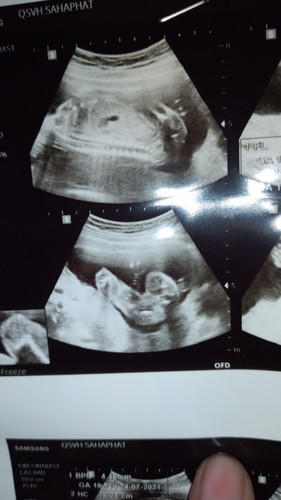

หมอนัดไปซาวดูเพศวันนี้ หมอบอกเพศหญิง 90% แม่ๆช่วยดูให้หน่อยค่ะว่า

เพศหญิงจริงมั้ย

หญิงค่ะ